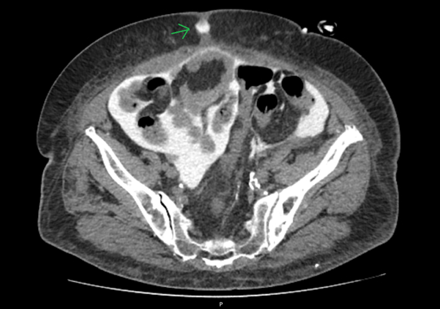

To assess for a possible peri-catheter leak and rule out a catheter fracture, a computed tomography (CT) scan was performed with contrast infusion into the peritoneal cavity (Figure 2 and Figure 3). The protocol included a standard non-contrast CT scan followed by a 2 h dwell of 1.36% glucose dialysate to which 100 ml of contrast was added, comprising a total of 2 liters of infused fluid.

Figure 3.

A second CT scan was performed afterward. Imaging showed dialysate drainage through the midline in the periumbilical region, where there was also significant adipose tissue densification. Intraperitoneal pressure was not measured at this time.